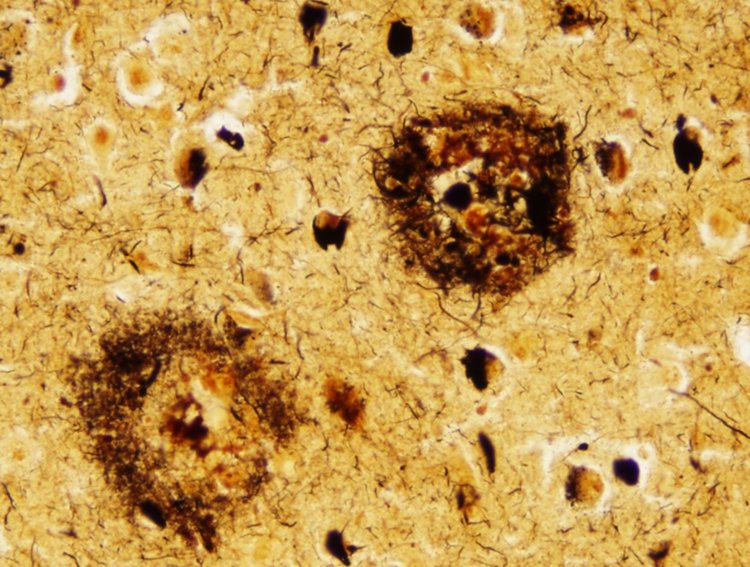

Моделиране in vitro в лабораторията показало, че холестеролът ускорява агрегацията на амилоид бета (Аβ) молекули с фактор 20. Счита се, че това натрупване на амилоид е решаващо за разрушаването клетките в мозъка при Алцхаймер .

Други проучвания вече свързаха по-високия холестерол с по-висок риск от болестта на Алцхаймер. Новото изследване показва за пръв път как молекулите на холестерола могат да действат като катализатор, като причиняват превръщането на амилоид бета в плаки.

Изследователите наблюдавали как молекулите амилоид бета се прикрепят към липидните клетъчни мембрани, които съдържат холестерол, давайки на молекулите начин да се слеят заедно и да започнат да се агрегират. Това би помогнало да се обясни защо амилоид бета, който обикновено присъства в много ниски нива в мозъка, може внезапно да започне да нахлува върху здрави неврони, като стартира Алцхаймер.

"Тази работа ни помогна да ограничим конкретния въпрос в областта на изследванията на Алцхаймер", казва Вендроскуло. "Сега трябва да разберем по-подробно как се поддържа балансът на холестерола в мозъка, за да се намерят начини за инактивиране на агрегацията на амилоид бета (образуването на плаките, характерни за заболяването)."